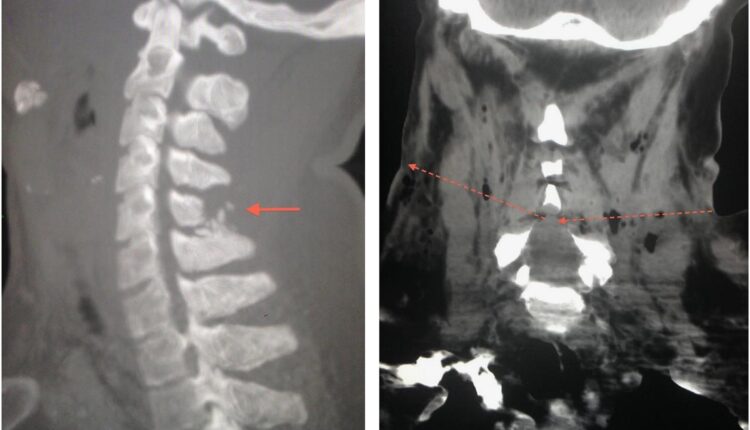

ବ୍ରହ୍ମପୁର : ବ୍ରହ୍ମପୁରରେ ଆଇନୀଜୀବ ପୀତବାସ ପଣ୍ଡାଙ୍କ ଆସିଲା ପୋଷ୍ଟମର୍ଟମ ରିପୋର୍ଟ । ପୀତବାସଙ୍କ ମେରୁଦଣ୍ଡରୁ ବାହାରିଥିଲା ୯ ଏମ୍ଏମ୍ ଗୁଳି । ଡାହାଣ ଛାତି ଉପରିଭାଗରେ ଲାଗିଥିଲା ଗୁଳି । ଛାତିରୁ ମେରୁଦଣ୍ଡ ହାଡ଼ ପଛପଟକୁ ଗୁଳି ଯାଇଥିବା ଡାକ୍ତର ସୂଚନା ଦେଇଛନ୍ତି। ଗୁଳିଟି ବହୁ ଶିରାପ୍ରଶିରା ନଷ୍ଟ କରିଥିବା ବ୍ୟବଚ୍ଛେଦ ରିପୋର୍ଟରେ ଉଲ୍ଲେଖ ଅଛି । ପୂର୍ବରୁ ଯୋଜନା ମୁତାବକ ସ୍ଥିତି ଉପରେ ନଜର ରଖି ହତ୍ୟାକାଣ୍ଡ ଘଟାଇଥିବା କୁହାଯାଉଛି ।

ସୂଚନାନୁସାରେ,ରବିବାର ରାତି ପ୍ରାୟ ୧୦ ଟା ସମୟରେ ପୀତବାସ ପଣ୍ଡା ନିଜ ଚ୍ୟାମ୍ବରରୁ କାମସାରି ଖାଇବା ନେଇ ବୈକୁଣ୍ଠନଗରରେ ଥିବା ତାଙ୍କ ଘରକୁ ଫେରୁଥିବାବେଳେ ଘର ନିକଟରେ ୨ ଜଣ ଦୁର୍ବୃତ୍ତ ବାଇକରେ ଆସି ତାଙ୍କୁ ଅଟକାଇବା ପରେ ଅତର୍କିତ ଗୁଳି କରି ଫେରାର ହୋଇଯାଇଥିଲେ । ତେବେ କେଉଁ ପିସ୍ତଲରୁ ଗୁଳି ଫୁଟିଥିଲା ତାହା ସୁନିଶ୍ଚିତ କରିବା ପାଇଁ ମେଟାଲିକ ପ୍ରୋଜେକଟାଇଲ ଭୁବନେଶ୍ୱର ଫରେନସିକ ଲାବକୁ ପଠାଯିବ ।